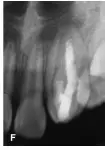

25個(gè)月后復(fù)診:X線片顯示i根尖區(qū)暗影消失,主根管根尖基本閉合,根尖愈合(圖1E)。復(fù)診時(shí)發(fā)現(xiàn)同為牙中牙的2牙體稍變色,牙髓熱測(cè)試無(wú)反應(yīng),診斷為2牙髓壞死,2開(kāi)髓后可探及內(nèi)陷根管的根尖止點(diǎn),測(cè)量工作長(zhǎng)度為22mm,25~30號(hào)擴(kuò)挫后Vitapex充填內(nèi)陷根管,磷酸鋅水門(mén)汀封洞(圖1F),調(diào)牙合消除2咬合干擾,囑以后每隔半年復(fù)診1次,適時(shí)行內(nèi)陷根管的根管治療。

圖1E:治療后25個(gè)月4主根管根尖閉合;F::2 Vitapex充填內(nèi)陷根管